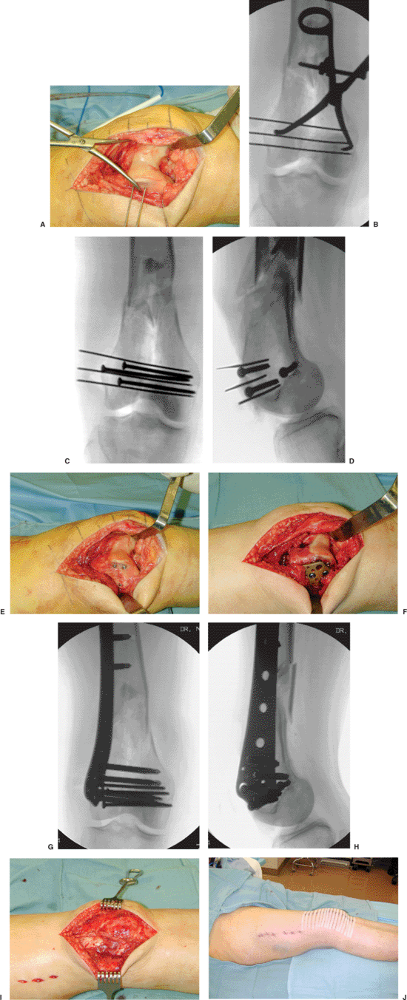

Figure 23.8. A.

The fracture is reduced through a lateral parapatellar arthrotomy. One advantage of this approach is that it allows for clamp application within the arthrotomy, as well as visualization of the medial and lateral femoral condyles for reduction of coronal plane fractures (if present). B. Multiple K wires can be placed to secure the reduction. C,D. Multiple lag screws can then be strategically placed to secure the reduction of the intercondylar fracture. These screws should be placed such that they allow placement of the lateral implant. E. In this case, a lateral locking plate is planned; therefore, these 3.5-mm screws are placed peripherally to allow placement of the plate. F. A plate can then be slid in a submuscular fashion and secured to the distal segment. G,H. The length and alignment are maintained as the implant is applied to the lateral femur. I. The lateral parapatellar arthrotomy is closed and (J) the appearance of the limb after wound closure. |